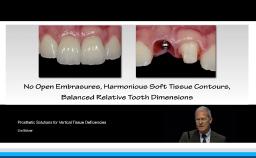

Ceramic materials are increasingly used for the fabrication of dental reconstructions. However, because there are so many options for fabricating ceramic prostheses, the selection of an ‘ideal’ material is becoming more and more complex. This lecture presents concepts for choosing the type of reconstruction, material, and method of fabrication for a highly esthetic outcome. Long-term survival rates, advantages, and limitations for new ceramic methods and materials - in particular high-strength ceramic zirconia - are presented in this lecture. The results of clinical studies comparing digital CAD/CAM and conventional workflows for fabrication of all-ceramic restorations are also presented.